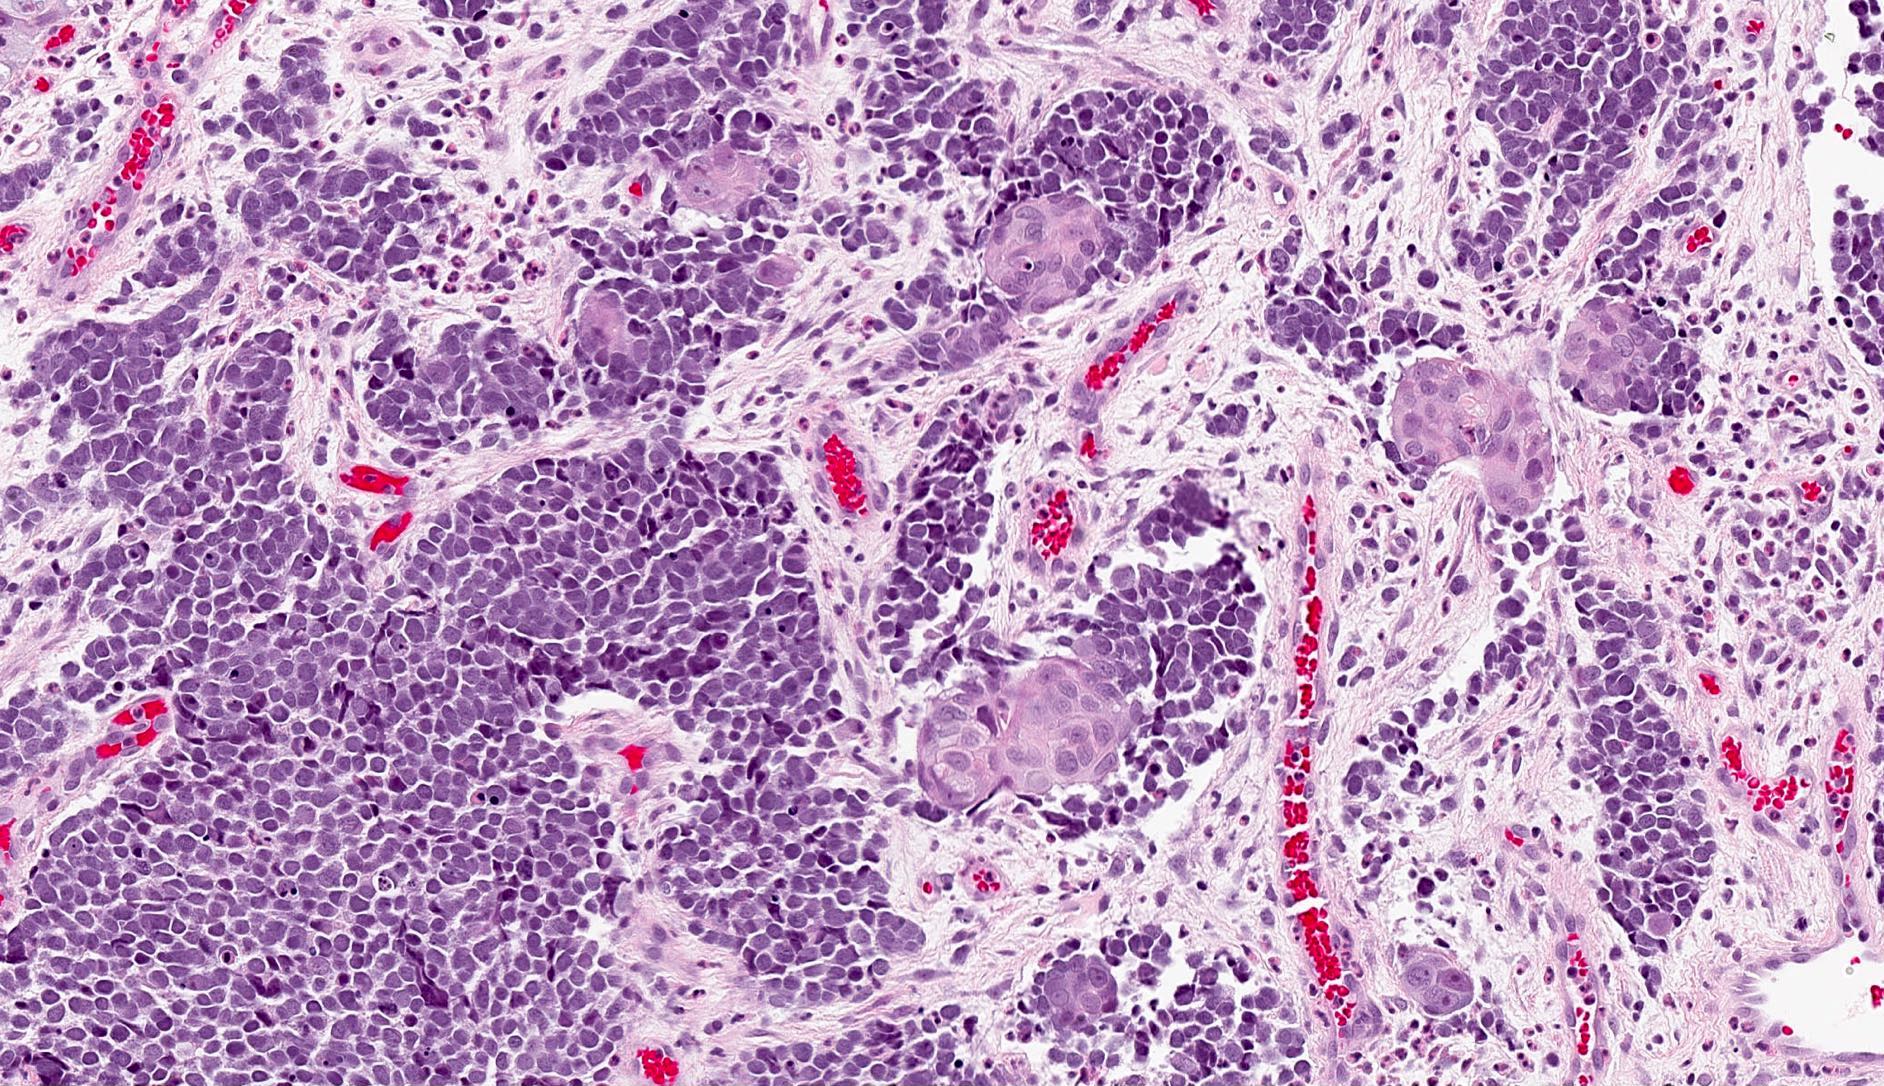

- Expansile, nodular or diffusely infiltrative tumor within the dermis, variably in subcutis

- Variable mixture of nodules, sheets, nests and trabeculae of neoplastic cells

- Generally, small round blue cell tumor with high N:C ratio, round / oval nuclei, finely dispersed chromatin (salt and pepper), indistinct nucleoli and scant cytoplasm

- Conspicuous mitoses and apoptotic bodies

- Variable nuclear molding and crush artifact

- Minority of cases feature neuroendocrine and other elements (combined Merkel cell carcinoma) such as divergent differentiation (e.g. squamous, sarcomatoid) or intimate association with other cutaneous neoplasms (most commonly in situ or invasive squamous cell carcinoma)